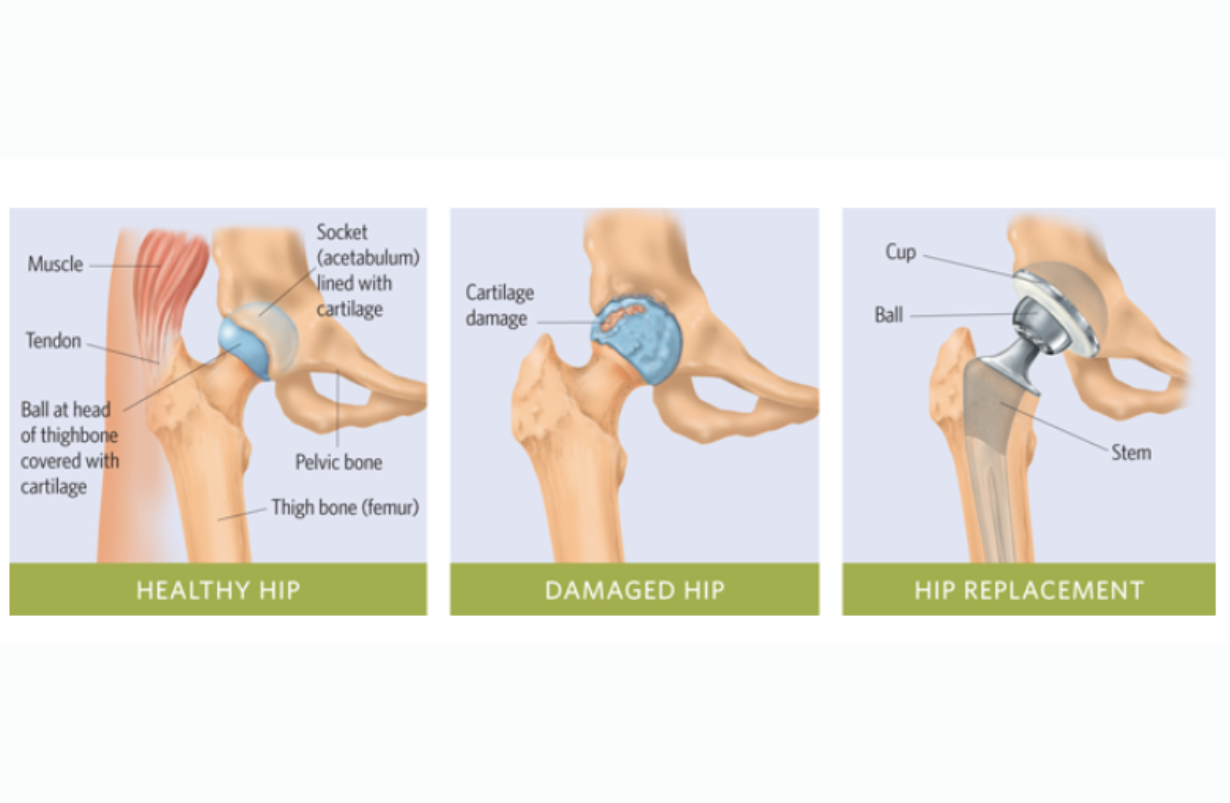

Anterior Total Hip Replacement

Surgical insertion of metal and plastic artificial joint, in which the incision is made in the front or side of the hip. Few or no muscles are cut; recovery is brief and nearly complete. In a fair number of cases, final recovery has a greater range of motion than before surgery. After 3 months, a cautious re-beginning of yoga is almost always fine. If there is doubt, contact the orthopedic surgeon. The poses to avoid are those that abduct and extend the leg. Upavista Konasana, Baddha Konasana, and Virabhadrasana I, II and III are contraindicated for longer, but may be cautiously approached after 6 months.

Arthritis Hip

Erosion of cartilage and dysfunctional reshaping of bones forming the hip joint.

Labral Tear of Hip

Separation of the strong, cartilaginous ring that surrounds and strengthens the acetabulum, the socket into which the ball of the femur or thigh bone fits. It usually occurs at the front of the hip joint. It frequently occurs in dancers and yoga practitioners, particularly with excessive back bending. The main effect is pain in the groin region or at the joint itself.

Posterior Total Hip Replacement

Surgical insertion of metal and plastic artificial joint in which the incision is made in the back of the hip. Gluteal and piriformis muscles are cut; recovery is slower. Give the surgery three months to heal. The basic restrictions are on flexion, adduction and internal rotation, which can be remembered as "FAIR." These limitations will continue for all of life, although some increase of each of these ranges is possible: mild to moderate flexion (enough to sit comfortably) and some adduction (not quite up to the full Gomukhasana or Garudasana), and some adduction (caution re: Ardha Matsyendrasana III or Marichyasana). Full Paschimottanasana should be approached very carefully and slowly, and in some cases leads to malfunctioning of the prosthetic hip, even requiring replacement of it.

Total Hip Replacement

Both the femoral (thigh bone) and acetabular (Hip socket) are surgically replaced by metal-ceramic or metal-plastic parts. The new thigh bone part has a long trochar that goes down into the marrow cavity of the femur for stability. There are basically two surgical approaches: the posterior, in which the gluteal muscles are cut, and the anterior, in which the tensa fascie latae is pulled to the side to allow insertion of the prosthesis. After the posterior approach, patients must be careful not to flex, adduct, and internally rotate the hip for a good long time, possibly from that time forth, to avoid dislocation. After the anterior approach, extension and abduction must be avoided for several months. Currently these surgeries give good range of motion and function, and last upwards of 20 years. Please see Anterior Total Hip Replacement and Posterior Total Hip Replacement for details.